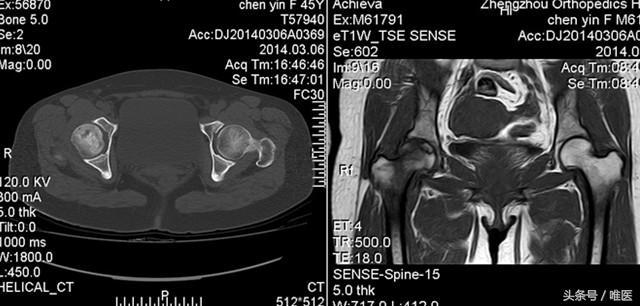

2、影像學(xué)檢查:醫(yī)生可能會通過X光、MRI等影像學(xué)檢查手段來確診股骨頭壞死。